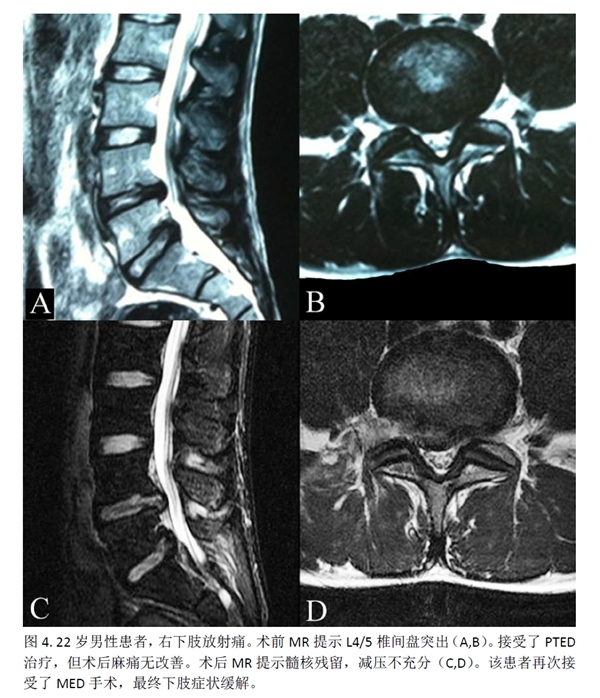

此外,2例(2.5%)PTED组患者及7例(9.59%)MED组患者出现新发患肢麻木感,但两组间没有统计学差异。MED组还有1例(1.36%)患者发生伤口愈合不良。PTED组有5例(6.25%)患者因复发/残留而需进行再次手术,MED组则为3例(4.11%)。再次手术率方面,两组之间没有统计学差异(p=0.818)。